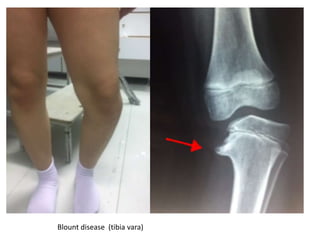

Knock knee

Blount disease (tibia vara)